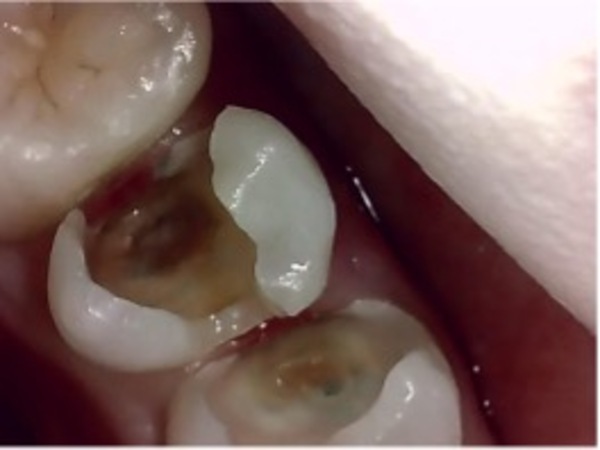

左のレントゲンには神経にまで達する大きな虫歯が見られます。

右の口腔内カメラの写真からは一見なにもないように見えますが、少し歯の色が全体的に黒くなっています。

④今回は事前にわかっていましたが神経が露出してきます。また歯茎から出血しているので止血しています。